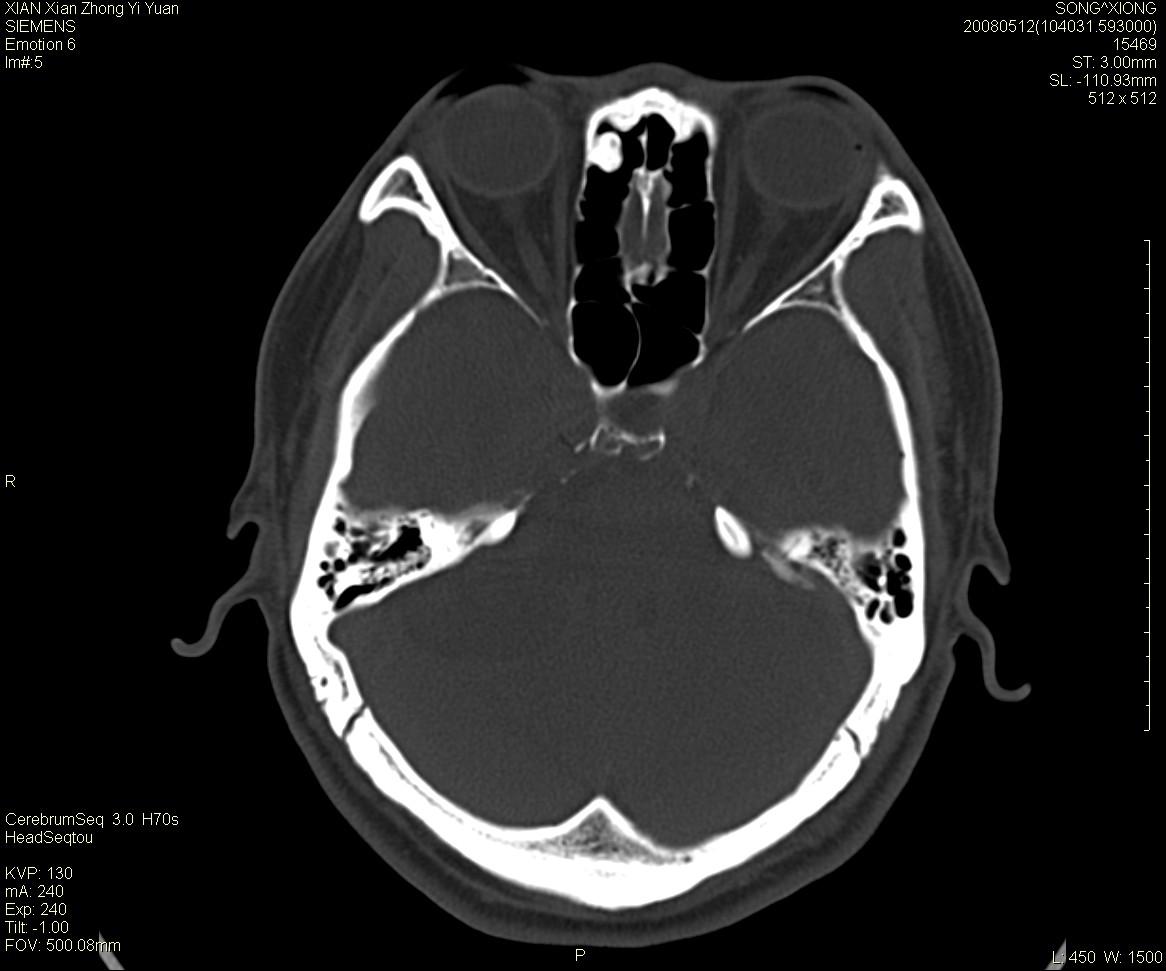

右侧内耳道慢性增宽,内耳道口出可见稍高密度影,桥小脑角池可见以较大低密度影,内缘较清,小脑、脑干、第四脑室受压、移位。

考虑:听神经瘤。

骨窗显示内听道扩大,考虑右侧听神经瘤